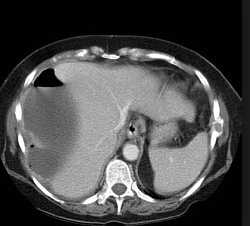

CT scan: Colonic wall thickening, fat stranding

Contrast-enhanced computed tomography (CECT) is the standard imaging modality for the evaluation of acute pancreatitis and its complications, including necrosis and vascular complications. Non-contrast CT scan can be used, however, it cannot assess for necrosis or vascular complications.